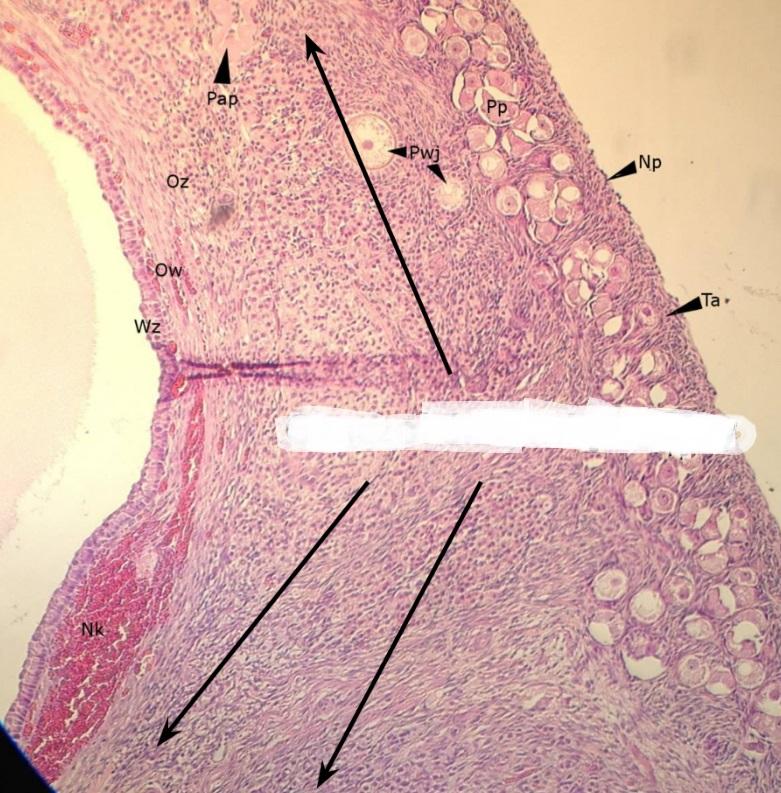

nabłonek sześcienny - płciowy (jajnik, kora)

Pytanie 470

pęcherzyk jajnikowy pierwotny (jajnik, kora)

Pytanie 471

pęcherzyk wzrastający bezjamisty (jajnik, kora)

Pytanie 472

pęcherzyki dojrzewające jamiste (jajnik, kora)

Pytanie 473

pęcherzyk Graafa (jajnik, kora)

Pytanie 474

pęcherzyk atrezyjny (jajnik, kora)

Pytanie 475

błona biaława (jajnik, kora)

Pytanie 476

gruczoły śródmiąższowe (jajnik, kora)

Pytanie 477

warstwa ziarnista pęcherzyka (jajnik, kora)

Pytanie 478

osłonka wewnętrzna - obfita w komórki (jajnik, kora)

Pytanie 479

osłonka zewnętrzna - z dużą ilością włókien (jajnik, kora)

Pytanie 480